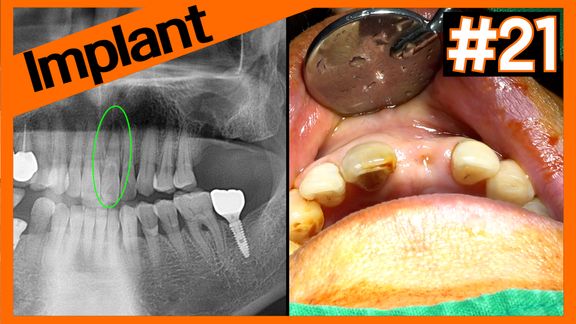

#16 Implant Removal & Immediate Placement

Online Surgery

Views 27